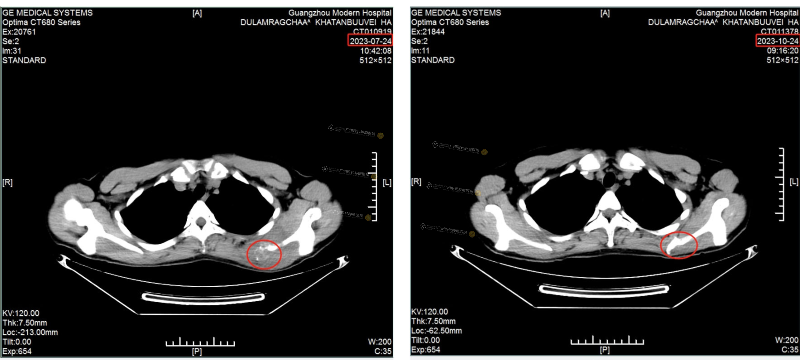

[The left picture shows the CT of the scapula in July: the size of the tumor is about 46mm×79mm and has invaded the scapula]

[The right picture shows the CT of the scapula in October: tumor disappeared]